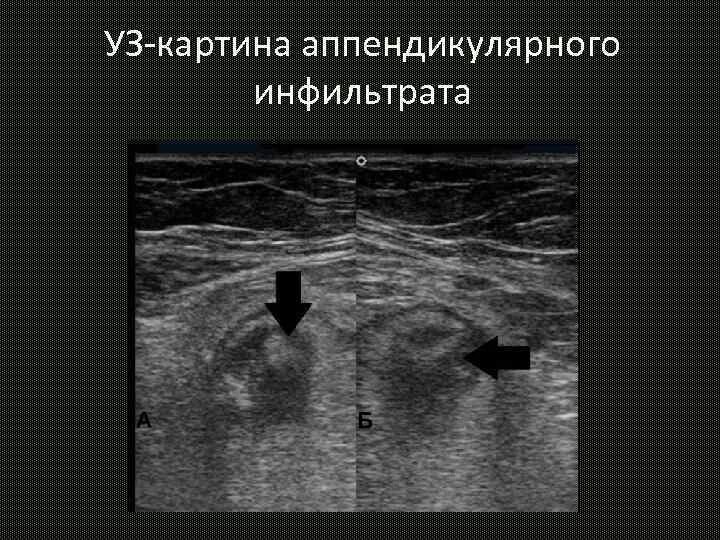

Абсцесс при аппендиците